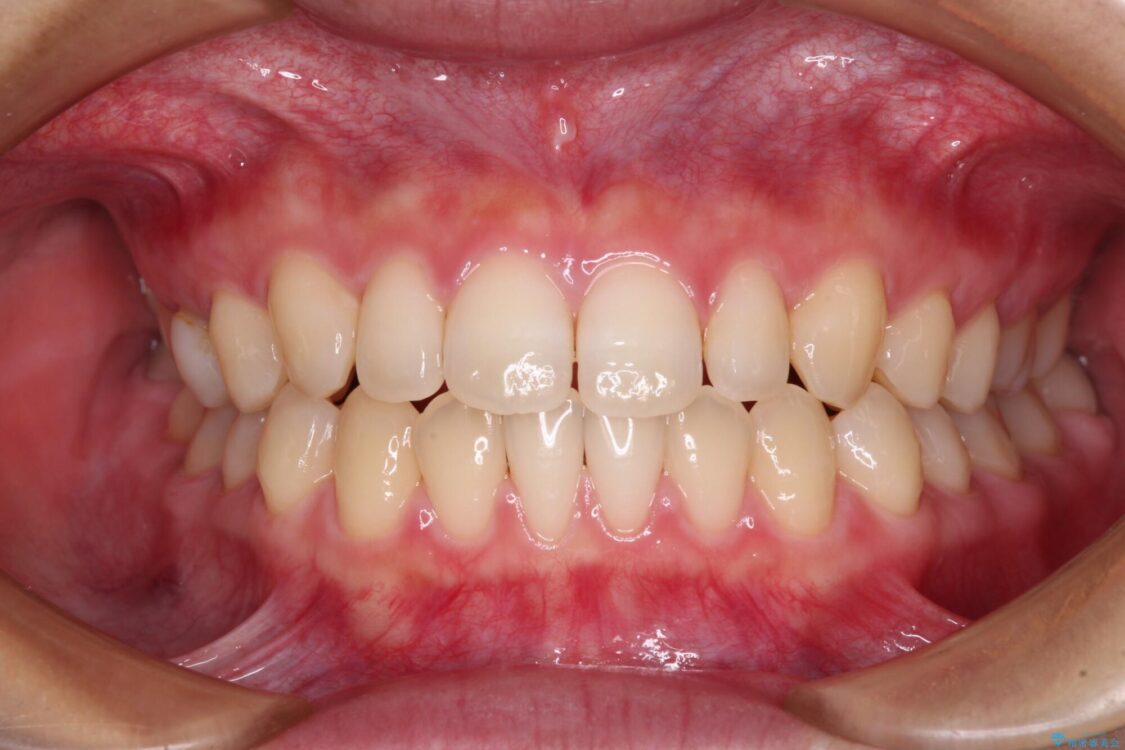

治療後

• 隙間だらけの歯列 インビザラインで改善 治療後画像

治療後について

空隙歯列(すきっ歯)は、舌の突出癖をある程度改善できたとしても、後戻りにより隙間が開きやすいと言われています。

裏側から細いワイヤーで保定するとともに、睡眠時のマウスピース装着を徹底していただくことで、後戻りを最小限にとどめます。